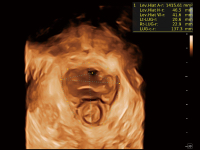

S-Fetus? 鳳眼

S-Fetus? 鳳眼(A4C切面)